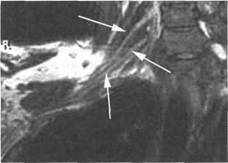

T2-BH(FATSAT).

I располагается позади. Иногда удается хорошо различить ин 10510f510k дивидуальное деление пучков. Ла-

MPT

STIR